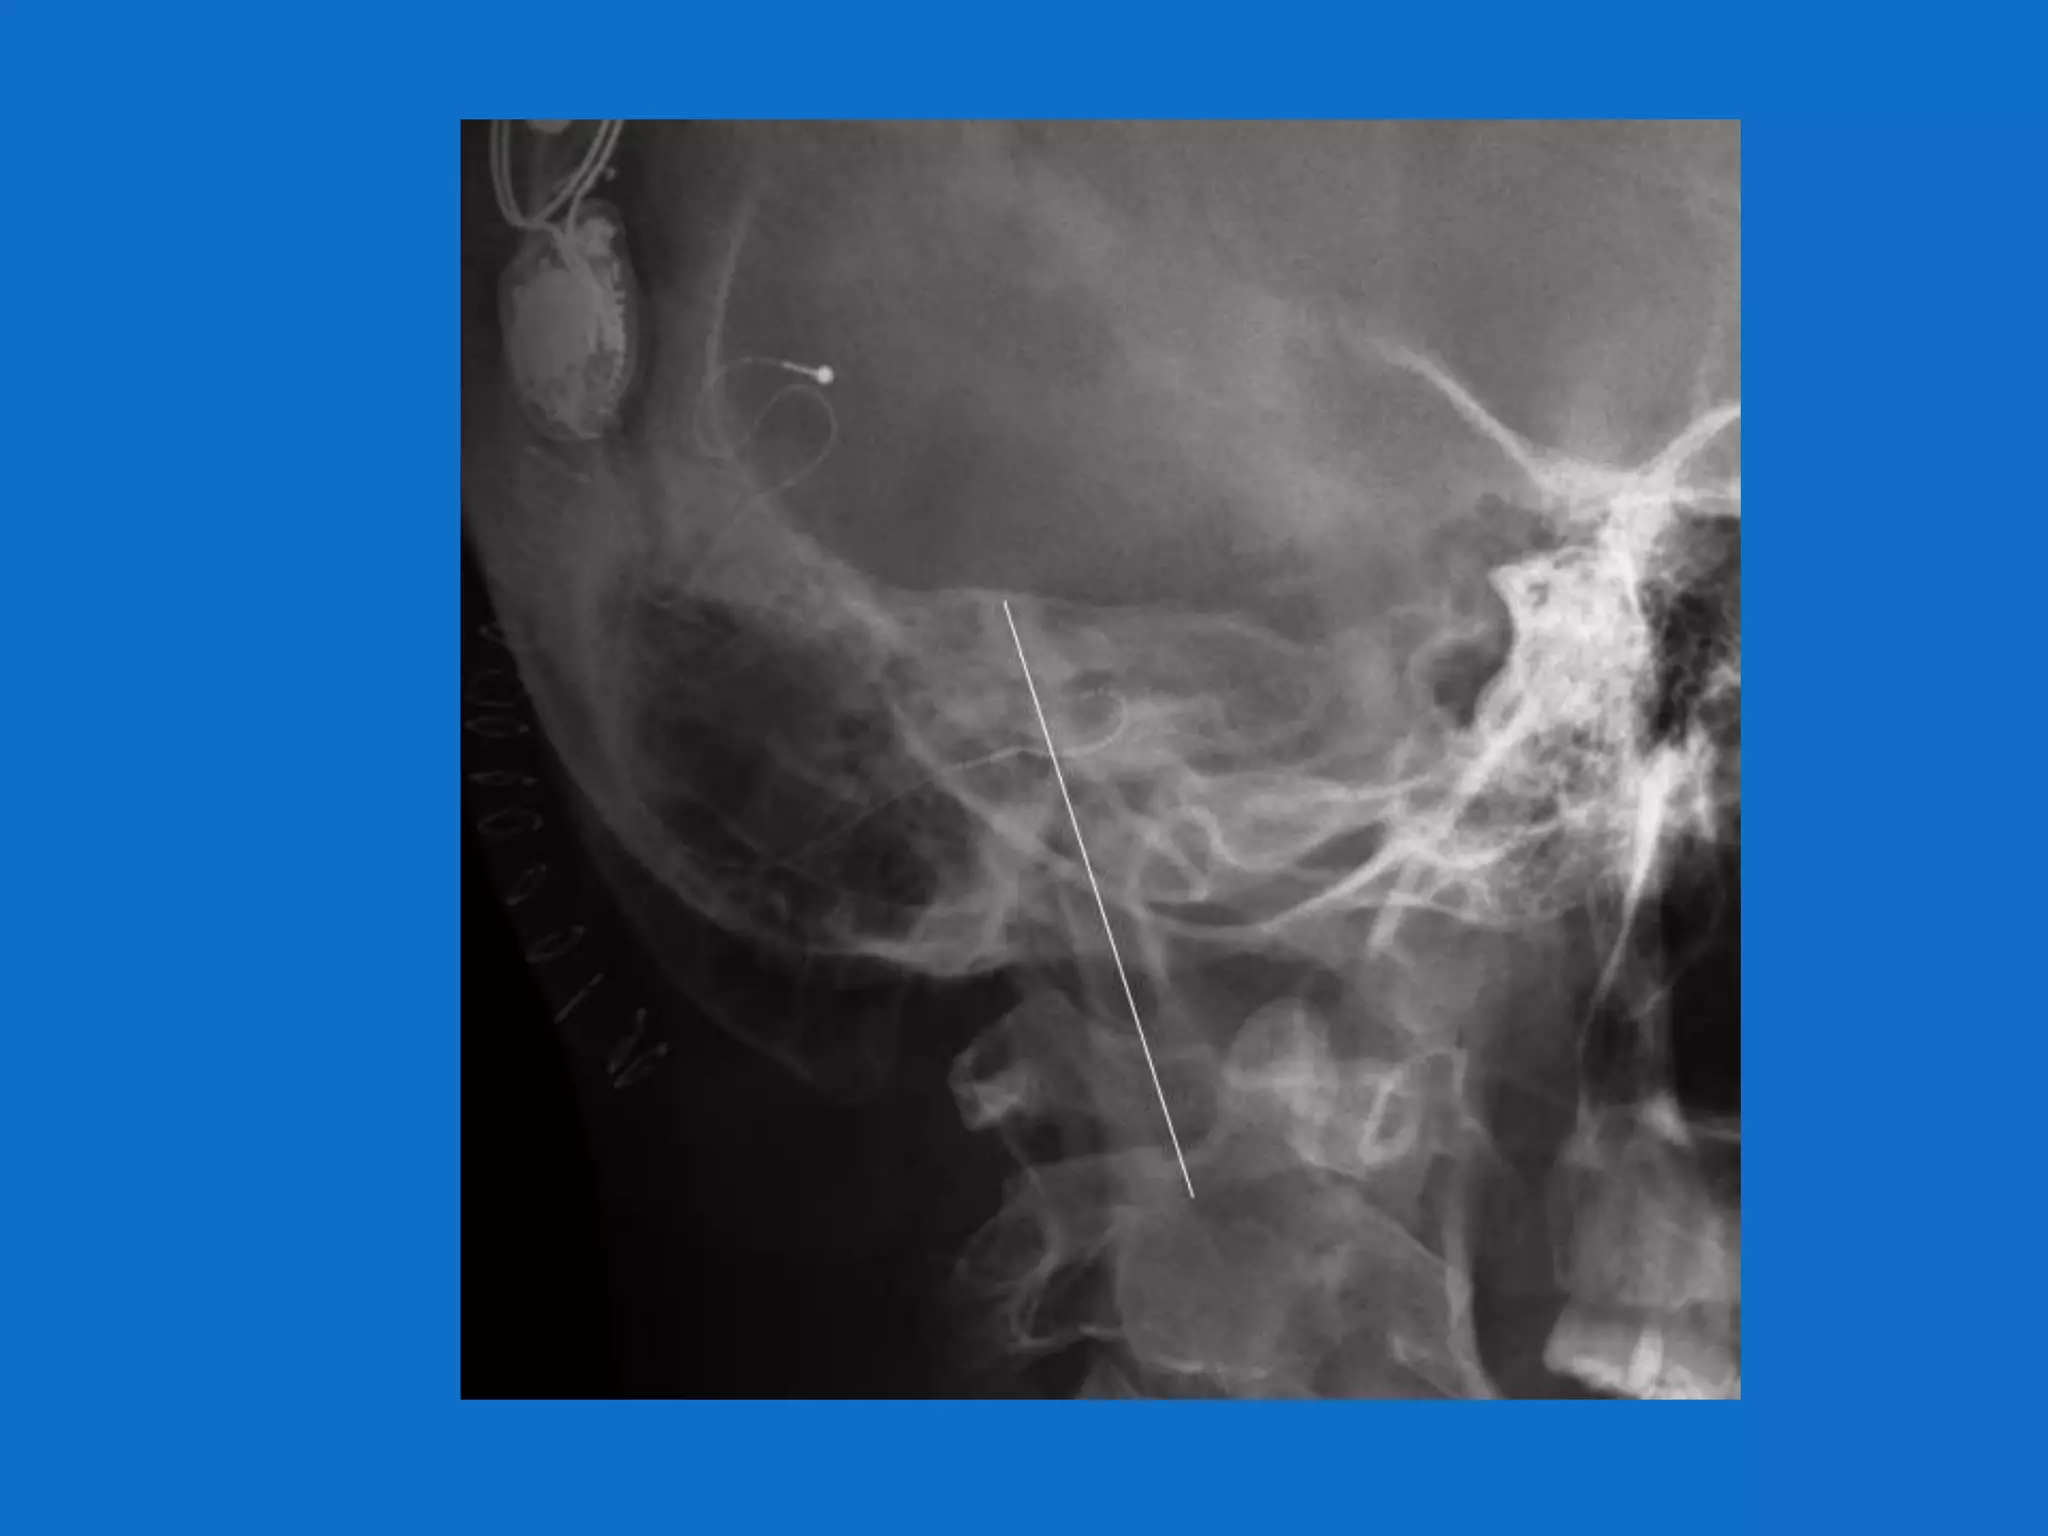

Surgery